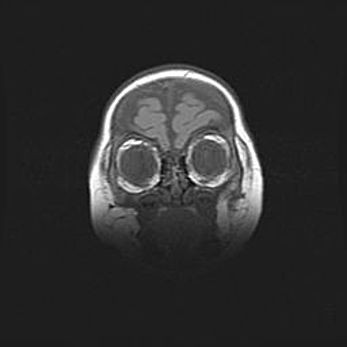

Церебральная ишемия II.

Возраст: 5 дней

Вес: 3400 г

Пол: женский

Окружность головы: 35 см

Срок гестации: 39 недель

Церебральная ишемия – это заболевание, характеризующееся недостаточностью (гипоксией) либо полным прекращением (аноксией) снабжения мозга кислородом по причине закупорки одного или нескольких сосудов. Это приводит к  что метаболическим расстройствам различной степени тяжести в тканях головного мозга, развитию коагуляционных некрозов и гибели нейронов.